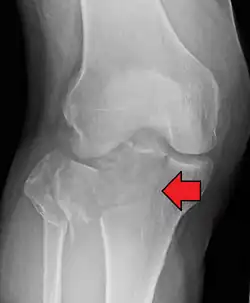

| A severe tibial plateau fracture with an associated fibular head fracture | |